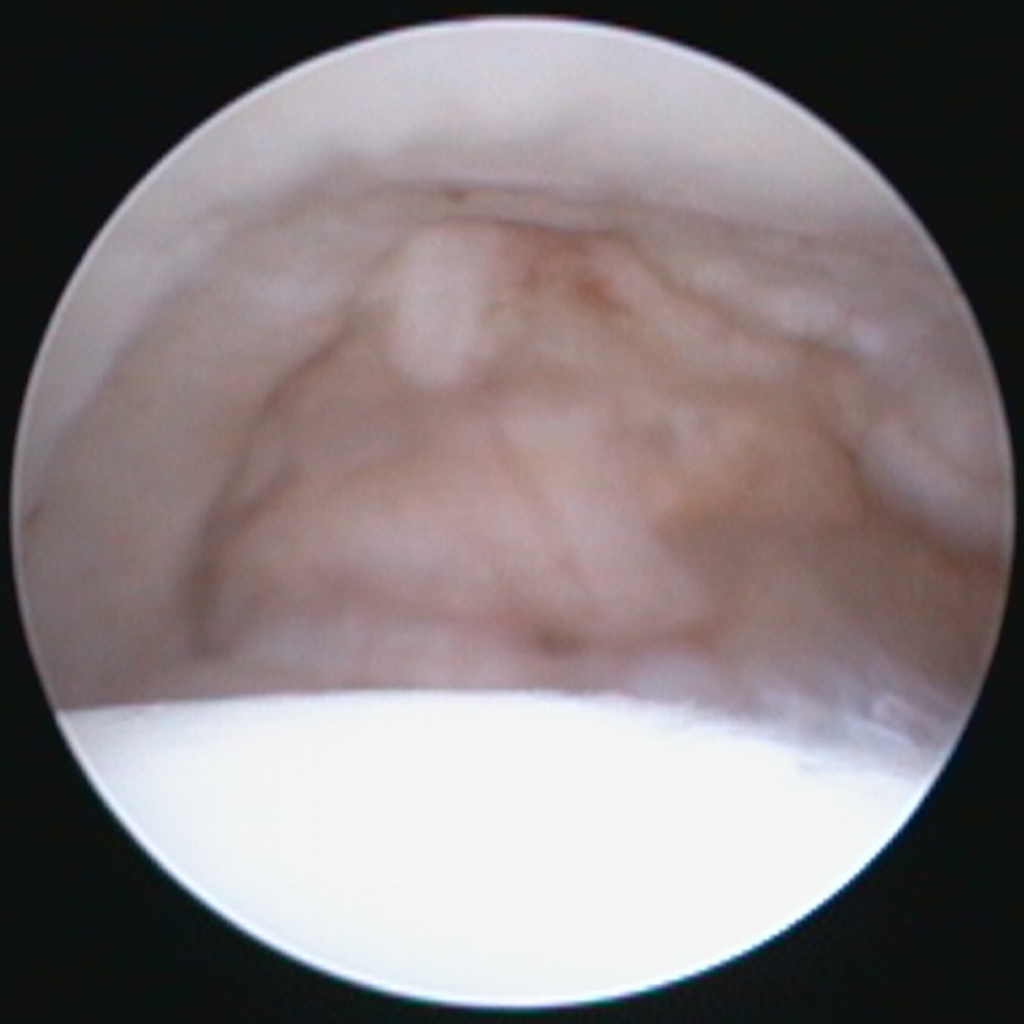

L’IRM n’est pas un examen de dépistage de routine, mais elle rappelle un point fondamental. Le cartilage peut être atteint avant que l’os ne montre des remaniements visibles en radiographie. Dans des contextes particuliers, l’IRM permet d’évaluer les tissus articulaires non osseux et de mieux comprendre certaines douleurs précoces ou atypiques. L’arthroscopie, quant à elle, permet une visualisation directe des surfaces cartilagineuses et peut être indiquée dans des situations ciblées, généralement lorsqu’une décision thérapeutique est envisagée et que l’on souhaite documenter précisément l’état intra-articulaire.

Arthroscopie de la hanche chez le même patient : visualisation du ligament de la tête fémorale (ligament rond) apparaissant hypertrophié et frangé, avec un aspect remanié et une perte de tension fonctionnelle, compatible avec une atteinte liée à une instabilité coxo-fémorale marquée.